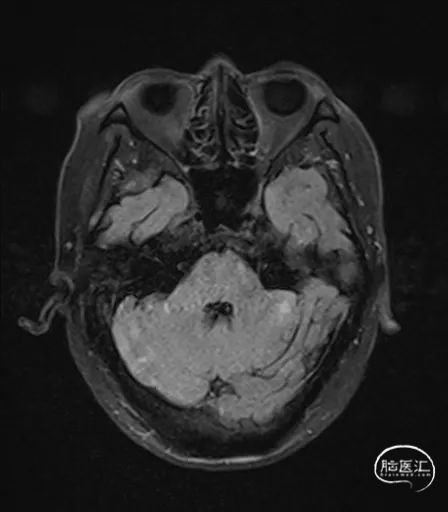

MRI提示小脑缺血性改变。

术后9天MRI: